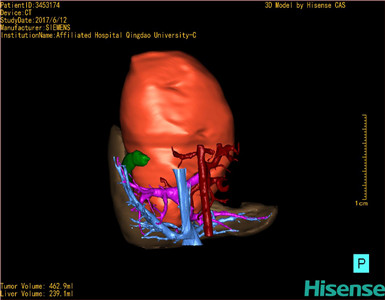

将0.625mm双源薄层CT资料的静脉期和动脉期Dicom格式文件导入海信CAS系统。

通过调节窗宽窗位调整CT序号,对肝实质,胆囊,下腔静脉,肿瘤,肝动脉、门静脉及肝静脉等进行三维重建;系统自动计算肝脏体积。

模拟手术操作,自动计算切除肿瘤体积。肝脏体积为310.9ml,肿瘤体积为437.7ml,肿瘤体积是肝体积的1.4倍,通过比对9-12月正常肝脏体积为321.13±118.91ml,通过术前模拟手术,精准判断切除后剩余肝脏体积能耐受,避免肝衰竭发生。

术前三维重建:

重建图片